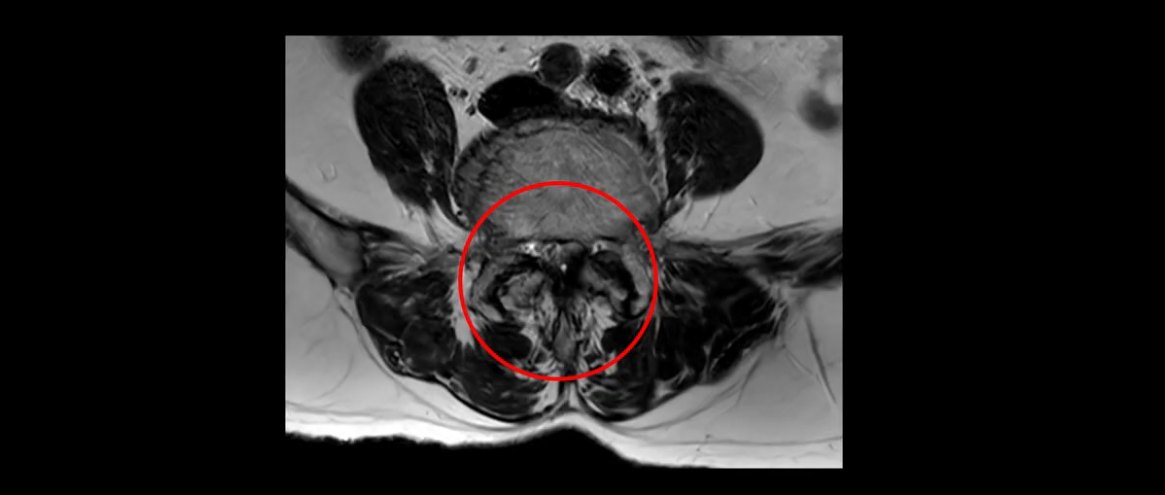

또 척추관협착도 매우 심합니다.

척추관이 심하게 좁아져 있습니다.

이렇게 여러 마디가 안 좋고 뼈도 밀려 나가 있으니까 나사박는 수술해야 하는데, 대학병원에서도 수술을 한 번에 못 하고 두 번에 나눠서 해야 한다고 들으셨습니다. 왼쪽으로 신경가지가 빠져나가는 추간공도 많이 좁아져 있습니다.

이렇게 신경 구멍들이 좁아져 있고 신경이 눌리니까 엉덩이와 다리가 너무 저리고 아파서 아예 일어서질 못하니까 휠체어를 타고 병원에 내원하셨는데요. 그럼 어떻게 이분처럼 신경이 눌려있는 환자분들을 수술 없이 치료해서 잘 걷게 만들고 엉덩이와 다리가 저리고 아픈 증상이 사라지게 할까요? 지금부터 설명해 드립니다.